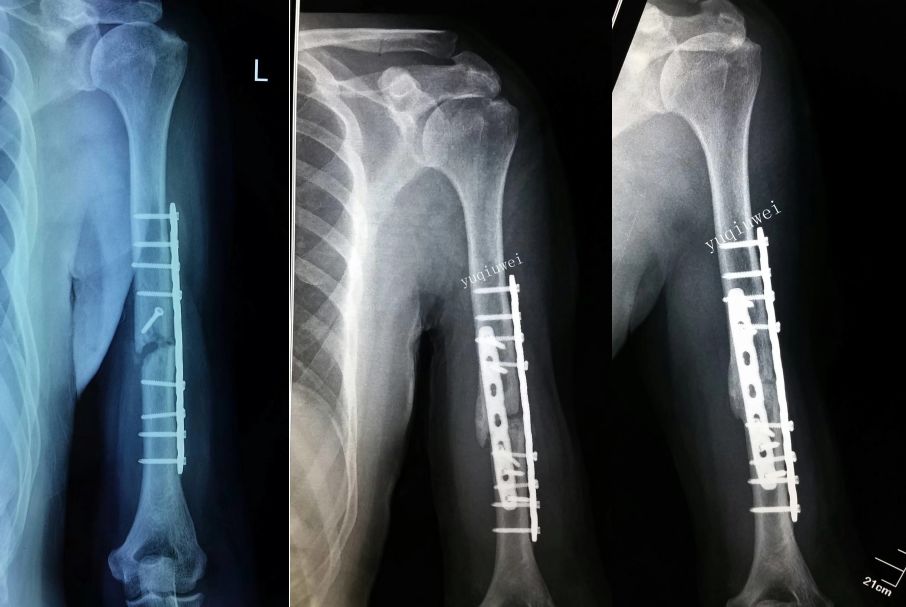

两处腓骨钢板多余(因为下胫腓骨联合没有损伤,特别注意不要犯这种错误)(髓内钉加阻挡钉首选,其次内侧长钢板,如果没有钢板用外固定架也可以)

胫骨远端简单骨折选用钢板固定没有实现坚强固定,钢板承受应力,孔处应力集中断裂

更换长钢板后愈合

应力集中断裂。内固定过于坚强,钉子粗,钢板与过度处应力集中(没有必要手术,必须手术可以用随内针加石膏固定)。

下一例:是胫骨骨折局部钢丝螺钉内固定太多干扰骨愈合,骨不连接钢板迟早断裂。

开放骨折,软组织损伤严重,骨不连接导致钢板断裂。应当在伤口愈合后及时干预植骨